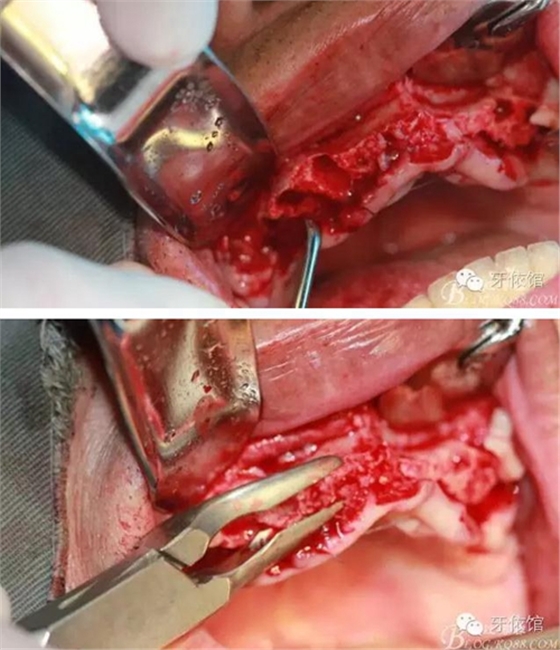

用擴(kuò)孔鉆去除切牙孔內(nèi)神經(jīng)纖維和血管

將前牙區(qū)取下的骨粉碎

將粉碎的骨填入上頜竇內(nèi)(未加骨粉,全部自體骨)